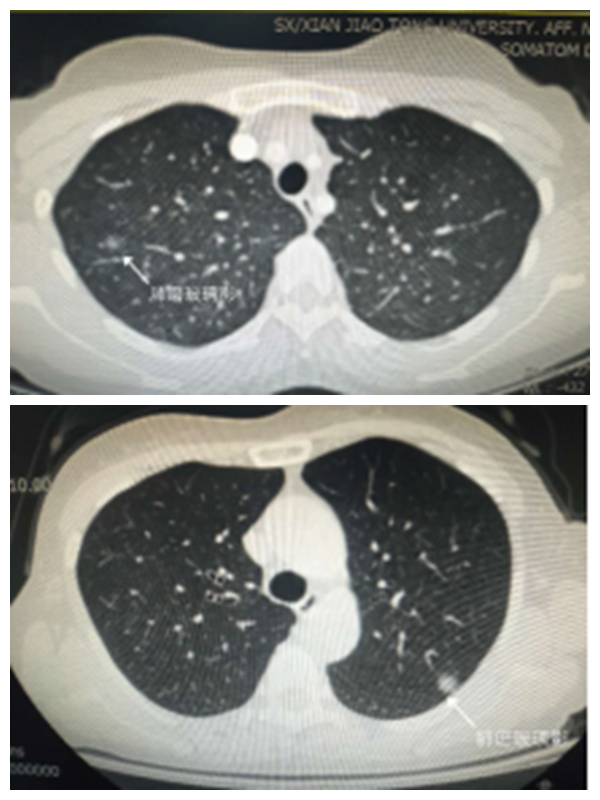

西安交通大学第二附属医院胸外科3D-CT重建下精准肺段切除术,是在原来熟练运用腔镜技术的基础上开展起来的。传统二维CT,无法准确定位肺结节位置,无法精准显示支气管、血管等空间结构,医生只能依据记忆中的图像,依靠丰富的手术经验和熟练的技术水平完成手术。3D-CT重建能立体、动态显示肺结节、肺动脉、肺静脉、支气管三维结构,就像汽车导航一样,提前规划,避免绕弯路,安全快速精准指导手术。对早期肺癌患者,肺段切除术可以达到不亚于肺叶切除术的疗效。与肺叶切除术相比,肺段切除术创伤更小,能最大程度保留患者正常肺组织,保护患者肺功能,大大提高了患者术后的生活质量。

王女士及张女士均为3D-CT重建下精准肺段切除术的受益者。她俩均在查体时发现肺部磨玻璃结节,到西安交通大学第二附属医院胸外科诊治。胸外科姜建涛教授经过详细检查,通过3D重建影像分析,经过团队严密术前讨论,与患者及家属耐心沟通,决定为患者进行“3D-CT重建下精准肺段切除术”,制定了精确的手术计划并于12月25日顺利完成精准肺段切除手术。和接受肺叶切除患者相比,肺段切除术后痛苦更小,肺功能保留更多,恢复更快,她们说:“根本没有想到,做个手术这么轻松!” 术后病理回报提示分别为“癌前病变”及“原位癌”,说明手术切除很及时,四天后两位患者均顺利康复出院。